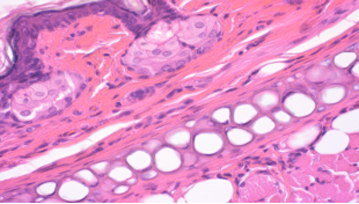

拥有屏障环境和普通环境的动物设施,建立实验动物临床病理和组织病理学实验室,具有丰富毒理学研究和GLP经验的技术团队,配备各领域专业团队,可提供技术服务可进行兔、豚鼠、地鼠、大鼠、小鼠等动物试验。

实验室团队具备丰富的动物毒理学研究经验和专业的技术能力。可提供食品、保健食品、药品、化妆品、消毒产品、医疗器械等领域的检测服务。